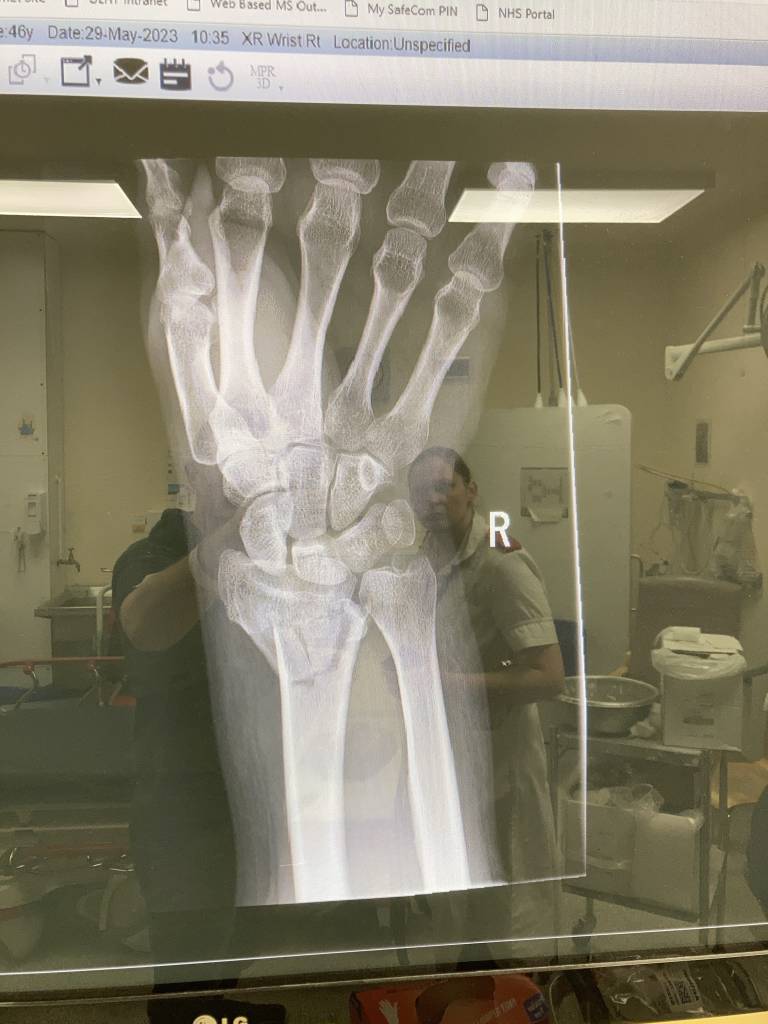

I've had a little fall and broken my radius, oops. The initial break was 30/05 and it was plated on 06/06, wound check and new cast on Friday. I'm pretty sure there will be a few people here that have done similar so please share recovery dos and don'ts.

Pics for context